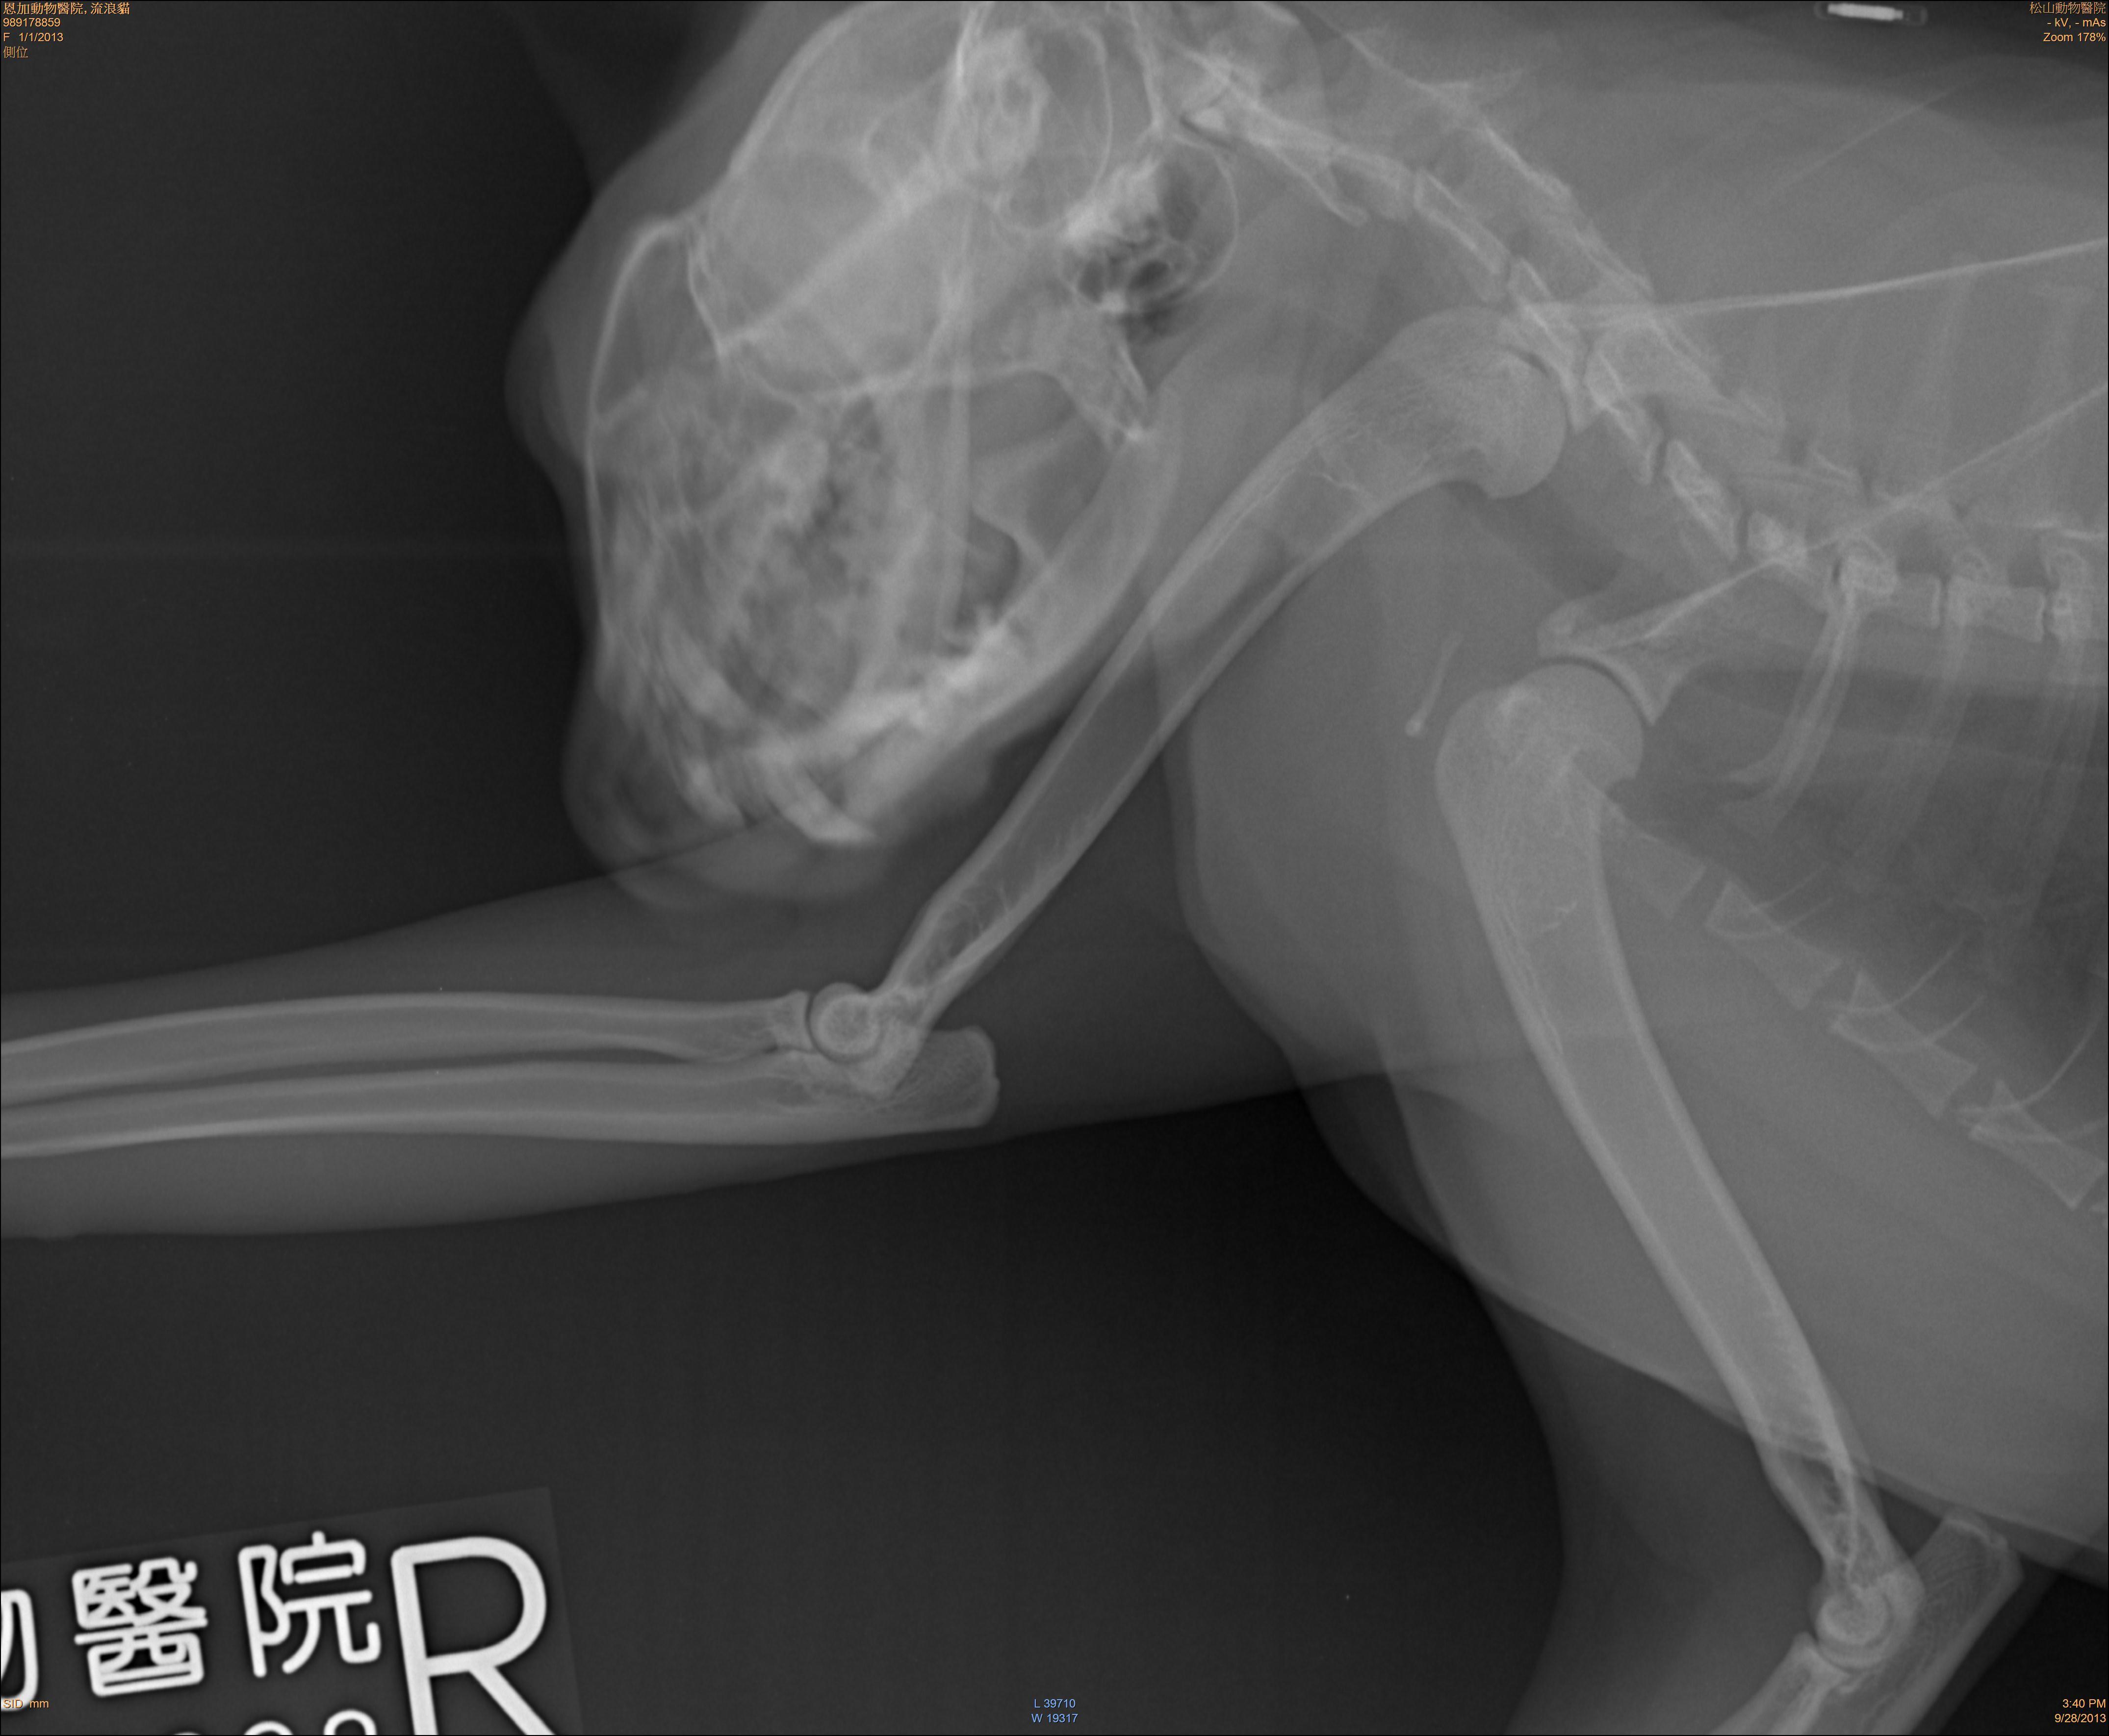

主題: 左前肢折斷的半橘猫 申請者姓名: 陳怡靜 花色: 申請日期: 2013-10-08 17:02:47 申請者部落格: 申請者臉書網址: 所在縣市/合作醫院: 台北市/恩加動物醫院 治療費用: 2500元 需求人數: 6人 已結案 (2014-01-10 17:58:16) 報名人員: clement(已付款)、Forest(已付款)、林醟鉗 x2(已付款)、Lulu Hsieh(已付款)、Anita Yin(已付款)、 候補人員: 動物病情說明: 這隻半橘街貓已餵養有五年已上的時間,平常每天都會出現要飯飯吃,連颱風天也會在車下等,昨天餵食食沒看到牠就覺得奇怪,很擔心!結果在更晚時去找牠喊了好久,才看到牠一跳一跳的出來,前腳有一隻是折的。便趕快將牠抓起來,抓了好久不進籠,最後用網子順利捕到,於今早送醫治療。

經醫生診斷後,這隻貓咪的腳沒斷,應該是扭到了,才會無法正常走路,經過幾天的休息及藥物的治療,醫生認為可以出院了,昨天晚上已放回原地;放回後隔一天就有出來吃飯,牠的腳已恢復到可正常行走。